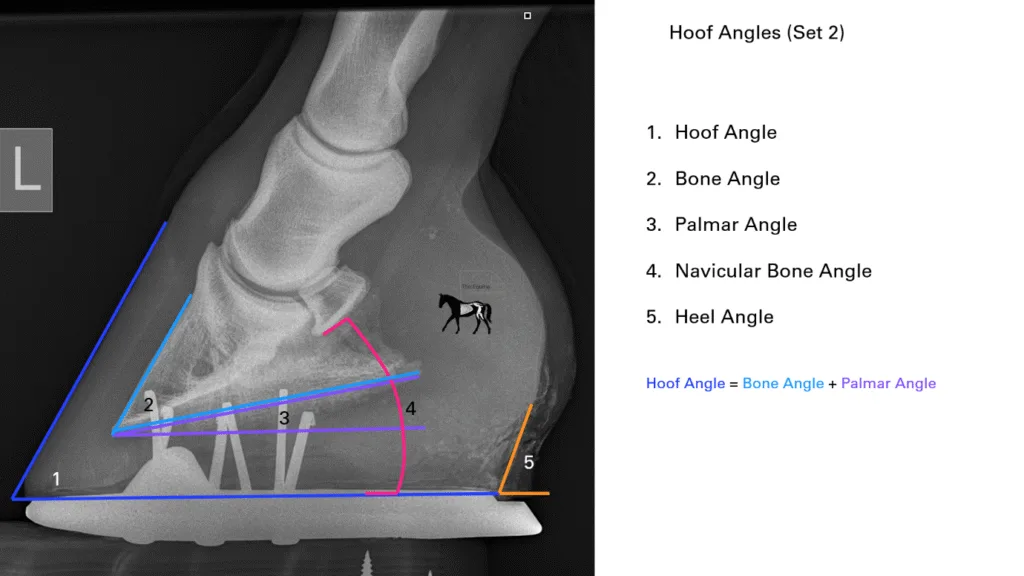

The orientation of the distal phalanx (P3, or coffin bone) within the hoof capsule is a central parameter in equine podiatry, farriery, and lameness prevention. Two key measures of this orientation are the palmar angle (PA) in the forelimbs and the plantar angle (PLA) in the hindlimbs. These terms refer to the angle formed between the solar margin of the distal phalanx and the ground surface, and they are routinely assessed radiographically (Figure 1).

Figure 1. The palmar/plantar angle is the angle made between the solar margin of the distal phalanx and the ground, seen here as angle 3. It has a correlational relationship with all the other angles.

What we do know is that there is a working relationship between some of the external and internal angles of the hoof. In Figure 1, we can see how the hoof angle is made up of the bone angle + the palmar/plantar angle, influenced by the heel angle and heel-to-toe height ratios. This relationship, however, means that due to differences in the range of bone angles that exist in the horse population, unless the individual’s bone angle is known, it has been historically accepted that PA cannot be calculated from external measurements.